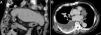

A 80-year-old man had history of hepatocellular carcinoma (HCC) status post right lobectomy of the liver; and prostate cancer, status post hormone therapy and radiotherapy. Elevation of alpha-fetoprotein (AFP) to 51.13ng/mL was noted during follow-up. The abdominal computed tomography (CT) yielded no local tumor recurrence over the liver (Fig. 1A). Unexpectedly discovery of right pleural effusion with a lot of pleural masses was found (Fig. 1B). The supplemental tumor markers of his prostate specific antigen (PSA) level was 0.661ng/mL (within normal range). Repeated thoracentesis for pleural effusion cytology and cell-block yielded negative for malignancy cell. Then, we performed a pleuroscopy, and a lot of cobble-like and protruding pleural masses are found (Fig. 2A). Peural masses of different sizes are revealed (Fig. 2B). Biopsy was performed and the pathology report showed carcinoma with hepatic origin (positive for arginase-1, hepar-1 and negative for calretinin).